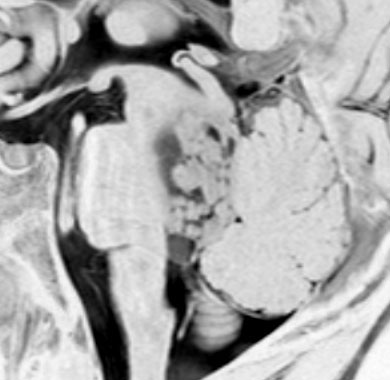

神経節細胞腫は放射線治療抵抗性

Tourette syndrome(音声と行動のチック,不随意運動)で発症した男児です。石灰化もありのう胞も伴う大脳基底核gangliocytoma grade 1で,摘出にはリスクがあると判断して46グレイ23分割の定位放射線治療をしました。しかし治療抵抗性で増大したために,上側頭溝からの経路で腫瘍を摘出(右の画像)しました。それ以来13年が経ちますが再発はありません。グレード1の神経節細胞腫は放射線治療抵抗性のものが多いと考えた方がいいし,より大きな線量を使用しても同じ結果なのでしょう。